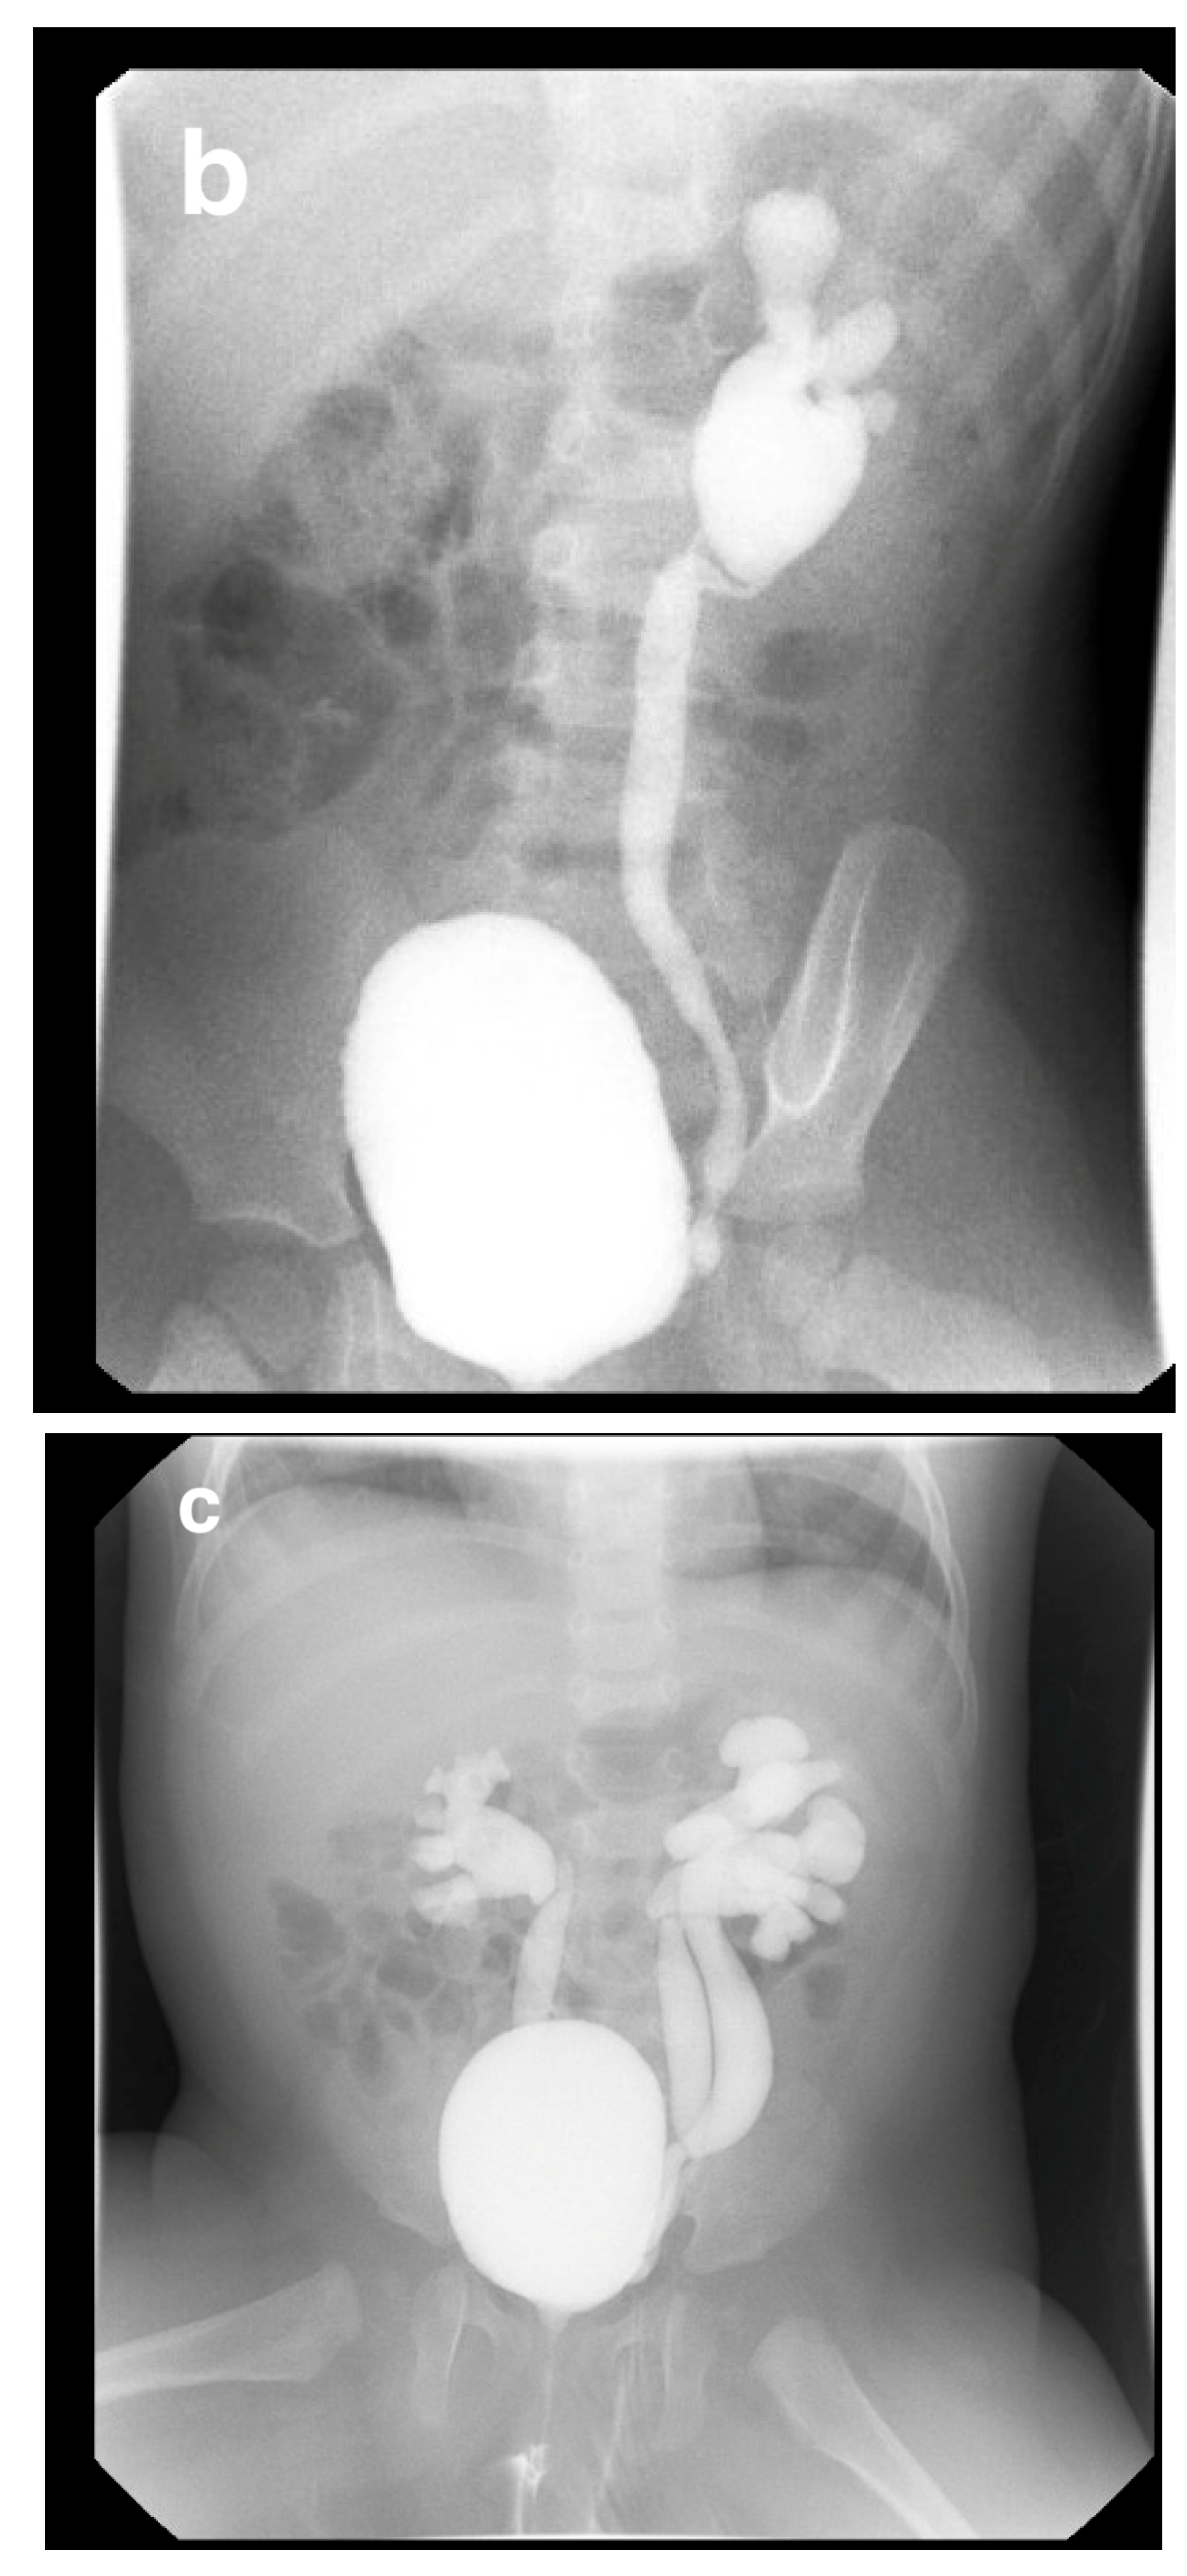

IVP is useful for evaluating ureteroceles, renal scarring, ectopic ureters, and obstructive disease (Figure 5), but has been largely replaced by US, CT, MRI, and renal scanning.

US is typically diagnostic for these conditions, as it can identify the location and structure of the kidneys. However, additional imaging, such as intravenous pyelography (IVP), CT, MRI, or renal scintigraphy, may be needed for further confirmation and to assess any associated abnormalities or complications (Figure 5).

Figure 5. IVP shows right crossed renal ectopia (indicated by arrows).

Medicina 61 00696 g005